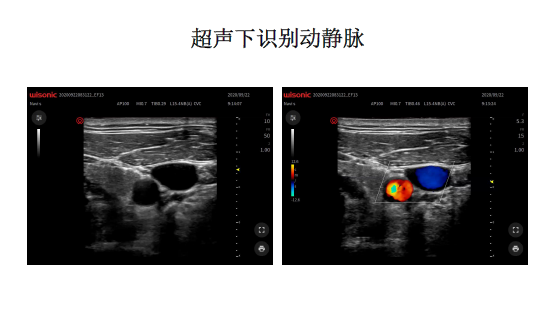

本期内容由陆海松大夫与大家共同学习【超声引导中心静脉置管和肺动脉导管的使用】。中心静脉穿刺置管是麻醉科医生的基本操作技能之一,使用超声引导有助于提高穿刺的成功率并减少并发症。肺动脉导管常用于重症患者的围术期管理,属于高级血流动力学监测的一种。

本课程介绍了超声引导的中心静脉穿刺,以及肺动脉导管的使用方法和注意事项,并回顾了肺动脉导管相关的文献。肺动脉导管可测得大部分血流动力学参数,但操作相关并发症较多,且缺乏证据支持能够改善患者预后。随着经食道超声技术和微创血流动力学监测技术的普及,肺动脉导管的应用逐渐减少,但在重症患者的循环功能评估方面仍发挥重要的作用。